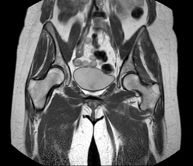

Exploració per a l'estudi de lesions a tendons, músculs i articulacions coxofemorals. Permet identificar de manera precoç l'artrosi de maluc. Resulta molt útil per detectar les bursitis i l'osteopatia dinàmica de pubis, freqüent en esportistes. La durada aproximada és de 20 minuts. No utilitza radiació ionitzant. - RM de Sacroilíaques

Prova diagnòstica no invasiva que consisteix en l'obtenció d'imatges d'alta definició anatòmica de la pelvis mitjançant l'ús d'un camp electromagnètic i ones de ràdio (amb un emissor i un receptor). No utilitza radiació ionitzant. Es realitza per a l'estudi de patologies d'úter, d'ovari, de trompes i de vagina, ja siguin d'origen tumoral, inflamatori o vascular. També permet valorar les estructures adjacents localitzades a la pelvis i la identificació de les seves alteracions. De vegades és necessari l'ús de contrast intravenós (Gadolini) per caracteritzar les lesions. - RM Pelvis masculina

Prova diagnòstica no invasiva que consisteix en l'obtenció d'imatges d'alta definició anatòmica de la pelvis masculina mitjançant l'ús d'un camp electromagnètic i ones de ràdio (amb un emissor i un receptor). No utilitza radiació ionitzant. No requereix preparació prèvia. En algunes ocasions necessita l'ús de contrast paramagnètic (Gadolini) per caracteritzar les lesions. Aquesta prova permet valorar òrgans com la bufeta urinària, la unió entre els urèters i la bufeta, la pròstata, les vesícules seminals, la uretra i els ossos de la pelvis, entre d'altres. - RM de Fetge